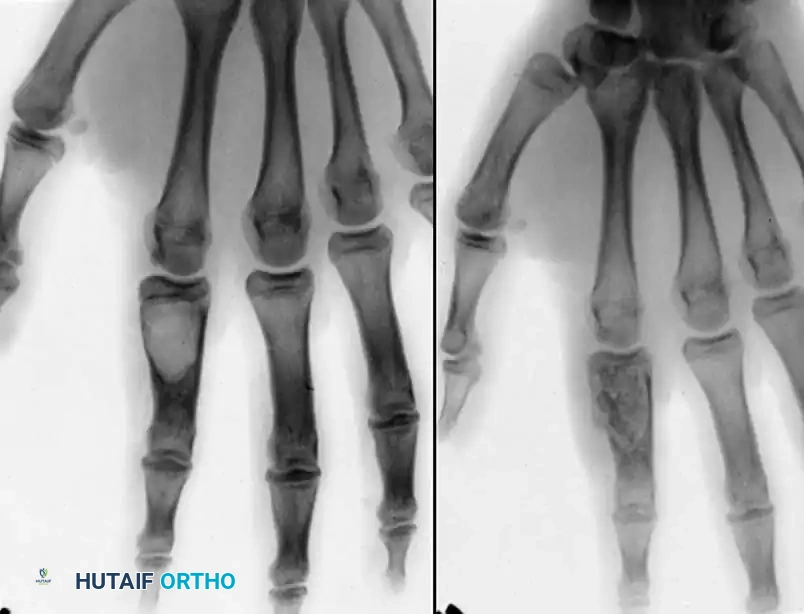

Surgical Excision and Recurrence

Excision is notoriously difficult. These tumors frequently wind in and around the flexor tendons, their synovial sheaths, digital nerves, and occasionally the extensor mechanism, sometimes encompassing three-fourths of

Associated Surgical & Radiographic Imaging